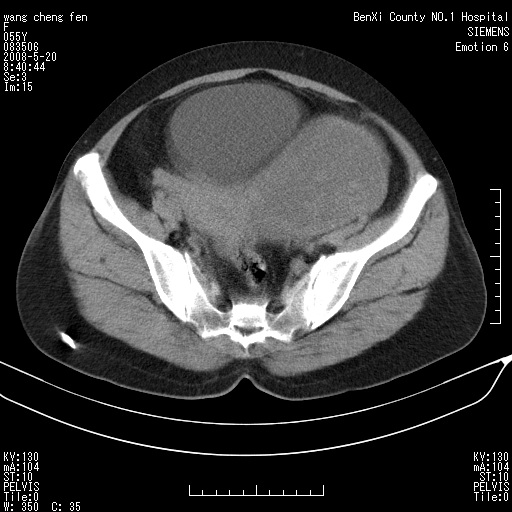

女、绝经后阴道流血3个月

左侧附件区巨大囊实性病灶,边缘光整,病灶囊壁较厚,增强示囊壁及实性部分明显强化,强化呈度与宫体实质大致相同,宫腔积液征像,未见盆腔积液等其他异常,考虑左侧卵巢囊腺癌,不除外囊腺瘤及浆膜下肌瘤坏死

左侧附件区巨大囊实性病灶,边缘光整,病灶囊壁较厚,增强示囊壁及实性部分明显强化,强化呈度与宫体实质大致相同,宫腔积液征像,未见盆腔积液等其他异常。绝经后阴道流血3个月,结合病史左侧卵巢囊腺癌首先考虑,宫腔扩大不除外累及。期待结果。

支持浆膜下子宫肌瘤.之前由于网络原因未看全图片,现在重看,宫颈见一类圆形低密度影,增强轻度强化,低于肌层强化,宫腔扩大,考虑宫颈癌伴宫腔积液可能性大.

囊实性肿块分隔厚度较大,厚薄不均,增强实性成分明显强化,有不规则阴道流血,卵巢囊腺癌可能性大。